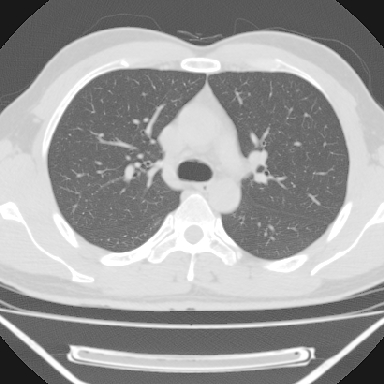

m 30 右胸痛10年

右上后纵隔旁软组织肿块影,与肺界面光滑,与胸壁呈钝角相交,提示肺外病变。位于肋骨下缘,边缘清楚,呈三角样指向与右侧椎间孔,但并示进入椎间孔;与对侧神经根对比,属同一走行方向。

考虑后纵膈良性肿瘤,神经源性肿瘤可能大。

鉴别:胸膜来源肿瘤。影像表现虽有肺外征象,但无胸水等相应佐证;再者,病史前10年,超长,与胸膜肿瘤不太吻合。

建议:再次查体,问清疼痛部位,如为1~2个肋间痛则神经源性肿瘤可能大,如疼痛较弥散,不按肋间分布,则可能为后纵膈其它来源肿瘤。

右上后纵隔脊柱旁见长椭圆形肿块,边界光整,与胸壁呈钝角。周围骨质未见异常。

考虑、1、后纵隔神经源性肿瘤;

2、不除外单发胸膜间皮瘤。

右上后纵隔脊柱旁类圆形肿块,边界光整,与胸膜呈钝角,首先考虑来源于肺外,神经源性肿瘤(神经纤维瘤可能大)。